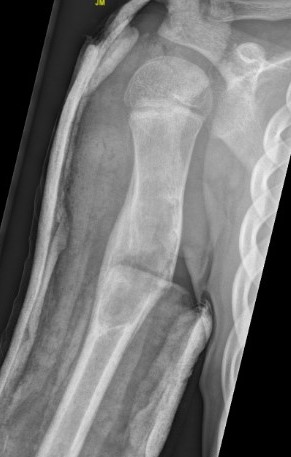

Location

90% humerus and femur

Proximal metaphysis where growth is greatest

X-ray

Well-defined lucency

- thin sclerotic rim

- usually central

- thinned cortex with slight expansion

- thin internal septa

- can be multi-loculated

Active - adjacent to growth plate / physis

Latent - separated from physis by normal bone